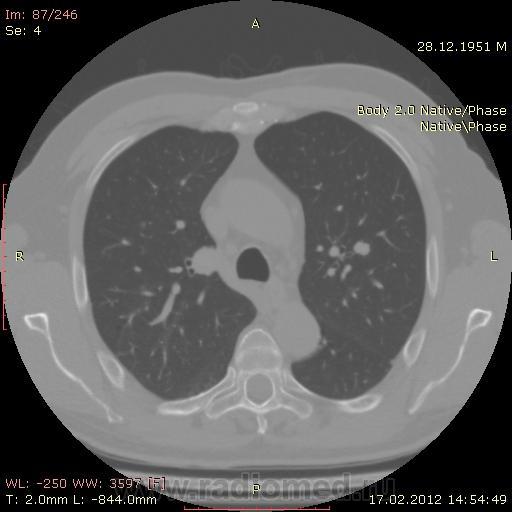

КТ.

В феврале 2012 года при очередном флюрографическом обследовании были обнаружены изменения в лёгких. По собственной инициативе было сделано КТ лёгких.

Согласен, наиболее вероятно метастазирование. В 2010 на боковушке, чуть ниже корня уже виден метастаз.